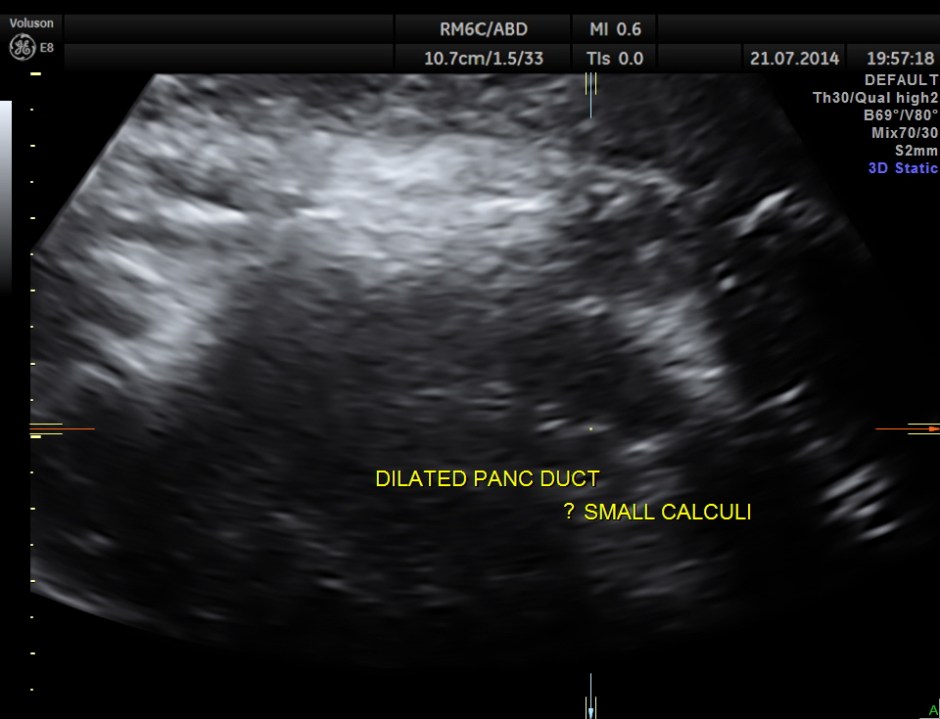

The following pictures show the pancreas.

Pancreatic duct is dilated prominently.

Pancreatic duct dilated.- 12.9 mms.

Pancreatic calculi are seen.